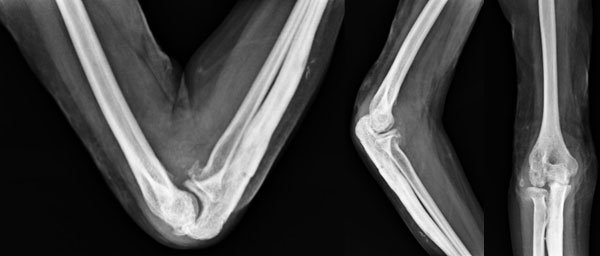

Movements Before Surgery

This 17 year old girl had stiff elbow as a result of an open inter-condylar fracture of humerus following side swipe injury. She underwent multiple surgeries for the same. When she presented to us the fracture had healed, skin graft was healthy but she had only of 50 degrees of arc of motion (40-90)